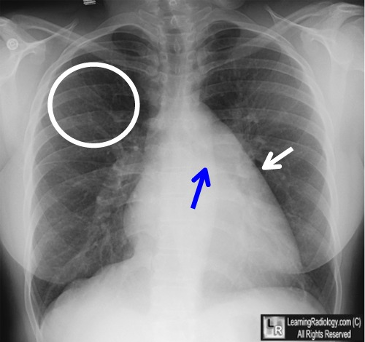

la niv. întregului hemitorace stg → opacitate extinsă, nesistematizată, de intensitate mare, omogenă

caracter retractil → tracționează traheea și mediastinul de partea afectată

fără bronhogramă aerică

duce la micșorarea spațiilor intercostale

la niv. hemitoracelui controlateral → hipertransparență compensatorie (emfizem)

DX: atelectazie prin NBP central endobronșic (pe bronhia principală stg)

DD: pleurezie masivă → caracter expansiv